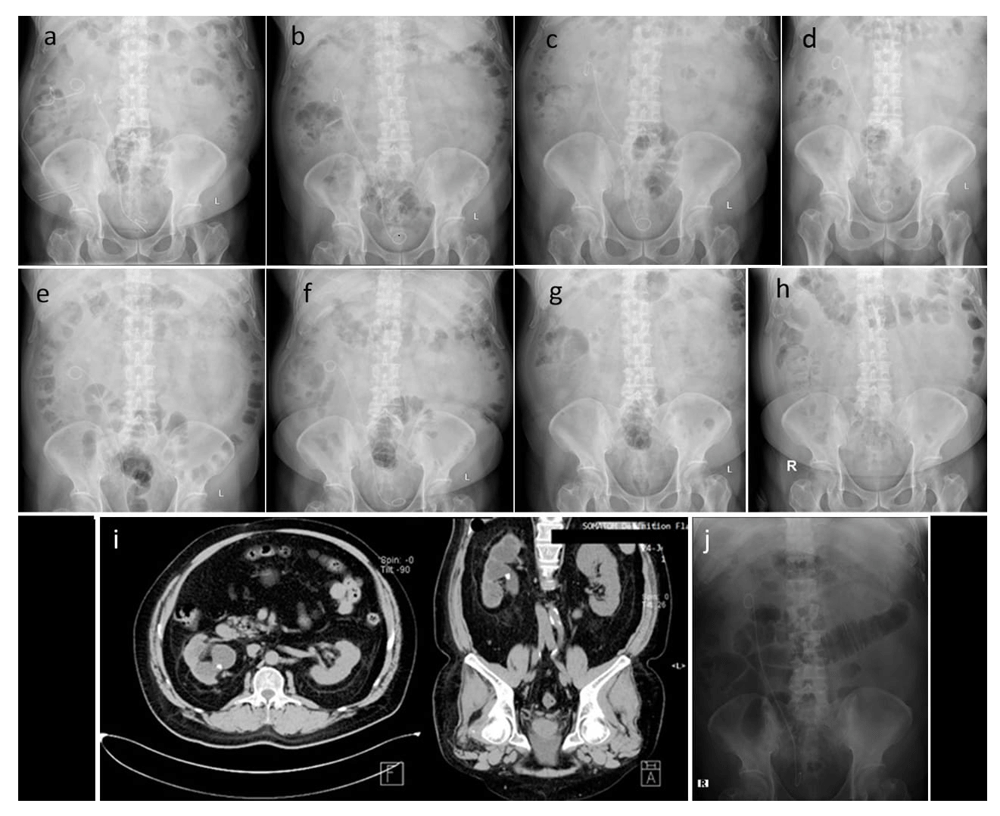

After right ureterorenoscopy, right nephrostomy, and right percutaneous nephrolithotomy in April 2016 (a), after ureterorenoscopy and percutaneous nephrolithotomy in June 2016 (b), after the second extracorporeal shock wave lithotripsy in June 2016 (c), after the third extracorporeal shock wave lithotripsy in July 2016 (d), after right laser ureterorenoscopy and replacement of right double J stent in July 2016 (e), after extracorporeal shock wave lithotripsy in October 2016 (f), double J stent removal in October 2016 (g), routine control in January 2018 (h & i), retrograde intrarenal surgery which shows no residual stone in June 2019 (j).

Extracorporeal shock wave lithotripsy (ESWL) was performed twice in June 2016, resulting in a decrease in stone size to 6 mm. (Figure 3c). Another ESWL was performed the next month (Figure 3d). In July 2016, he underwent a right laser URS followed by replacement of the DJ stent (Figure 3e). Three months later, another ESWL was performed (Figure 3f). Shortly after, the remaining DJ stent was removed. Plain abdominal X-ray still showed a residual right nephrolithiasis. (Figure 3g). In 2017, the patient was so depressed from the numerous procedures that he decided to end the treatment for his remaining stone. He admitted lacking spirit throughout the day since the failure of the last ESWL procedure and feeling that his stone would not be able to be cured, along with his continuous need for pain medication.

Almost two years later (January 2018), routine plain abdominal X-ray and CT urography showed no change on his right nephrolithiasis (Figure 3h, i). In June 2019, he was persuaded by his family to re-try stone management and had the last RIRS at another hospital to remove the remaining stone completely (Figure 3j). In November 2019, he visited our hospital for DJ stent removal and plain abdominal X-ray. Neither stone nor DJ stent were observed. The summary of the patient’s history of illness can be seen in Table 1.